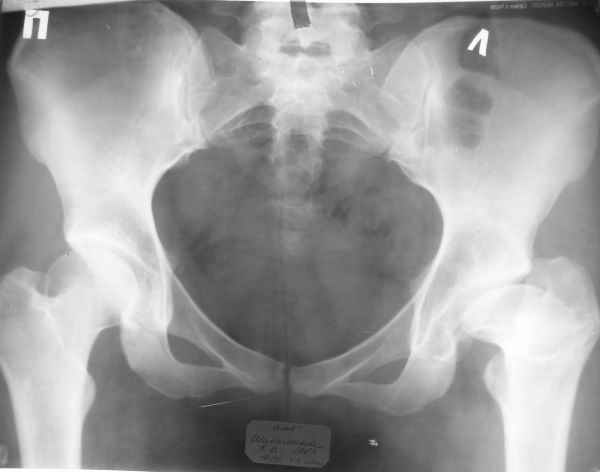

Пациентка 23 лет, доставлена в клинику с Диагнозом: Закрытый сегментарный оскольчатый перелом левой бедренной кости в верхней и средней трети. Травма в результате ДТП 10.03.2006г. Из анамнеза у пациентки диспластический левосторонний коксартроз, S-образный сколиоз 2ст. В 1999г в Кургане выполнялась остеотомия бедра в нижней трети и коррекция укорочения конечности на 3 см (рентгенограммы бедра и таза до травмы в приложении). До получения травмы пациентка ходила без боли с полной нагрузкой на левую ногу. Учитывая дисплазию левого ТБС, пациентке, вероятно, предстоит операция тотального эндопротезирования лев ТБС, что требует анатомичного восстановления проксимального отдела бедра.